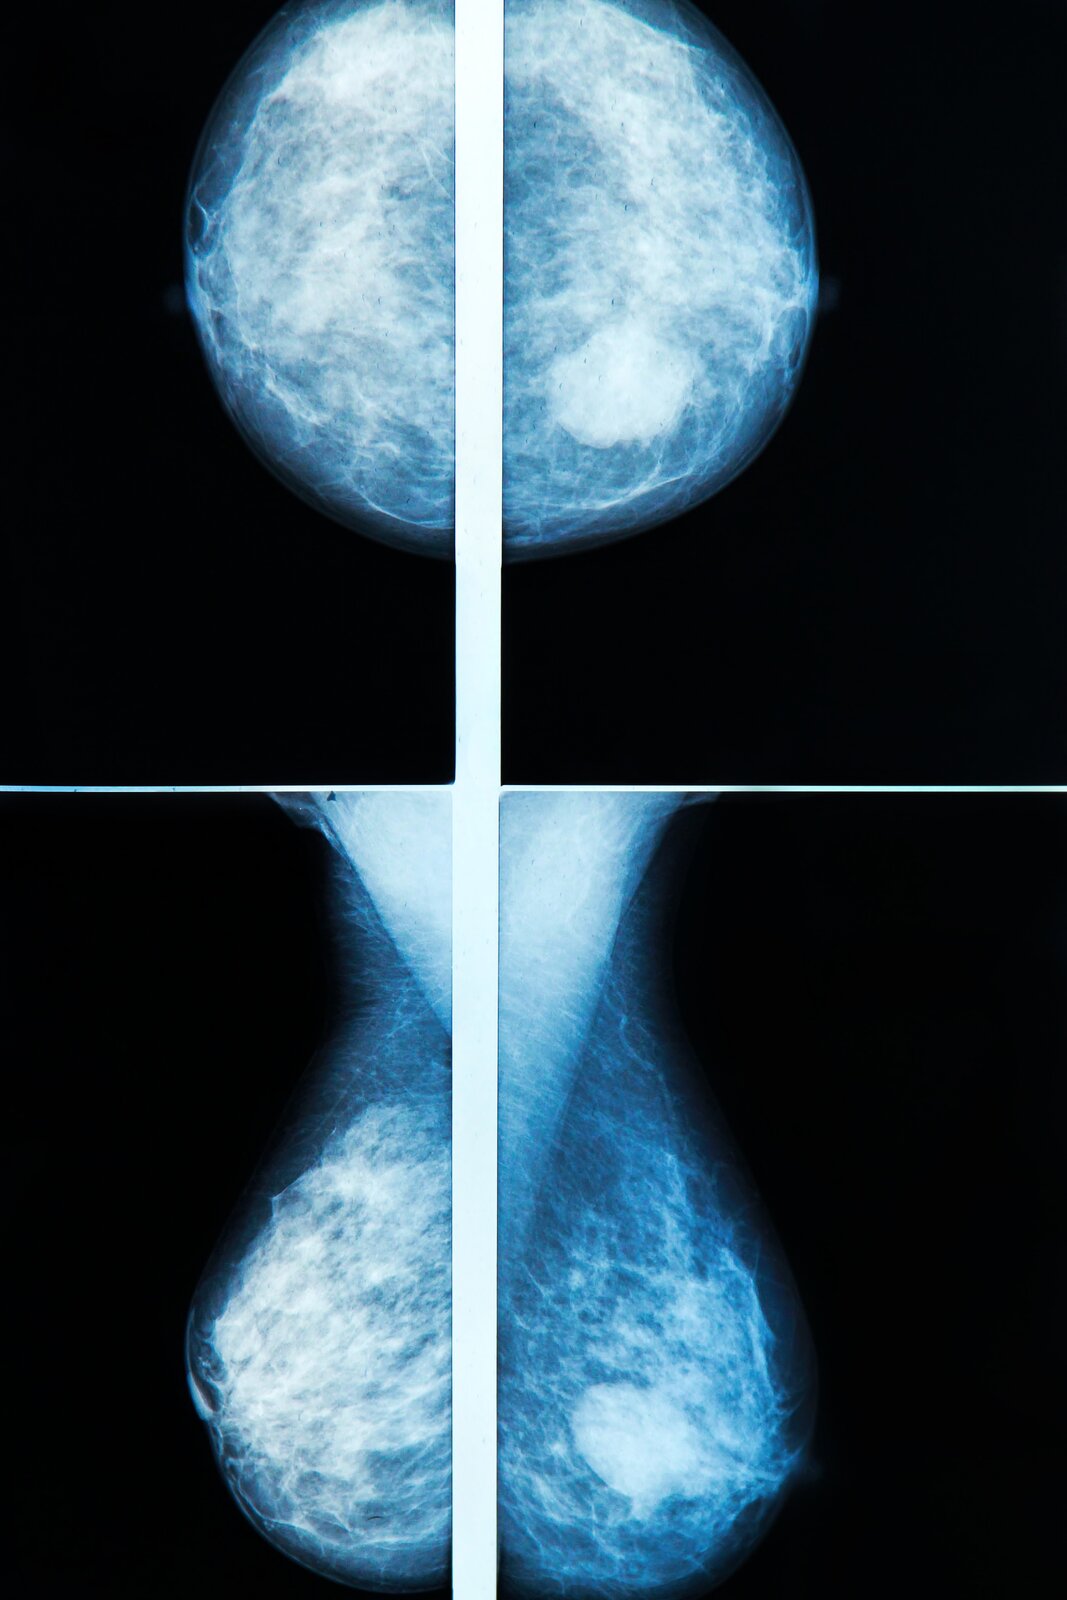

Każda kobieta powinna regularnie wykonywać mammografię lub USG piersi oraz badanie cytologiczne. Mammografia to badanie piersi z użyciem promieni rentgenowskich. Pozwala z bardzo dużą dokładnością stwierdzić nowotwór piersi na wczesnym etapie rozwoju, ale wykrywa też inne zmiany w piersi. Zalecana jest kobietom powyżej 40. roku życia. USG piersi to badanie z wykorzystaniem ultradźwięków. Wykrywa różnego rodzaju zmiany w piersi, w tym i guzki, nie tylko nowotworowe. W przypadku podejrzenia zmian nowotworowych konieczne są bardziej dokładne badania, m.in. mammografia. USG piersi zalecane jest kobietom po 20. roku życia. Do badania nie ma żadnych przeciwwskazań: jest całkowicie bezbolesne i nieinwazyjne. Można je również wykonywać u dzieci, jeśli jest taka potrzeba, a także u kobiet ciężarnych i karmiących piersią. Jeżeli w badaniach tych wykryje się zmianę, która może mieć charakter nowotworowy, należy pobrać fragment zmienionej tkanki, czyli wykonać biopsjębiopsję. Badanie cytologiczne pozwala wykryć raka szyjki macicy już we wczesnym stadium rozwoju. Przeprowadza się je z wykorzystaniem mikroskopu. Na szkiełku oceniany jest rozmaz komórek z materiału pobranego specjalną szczoteczką z szyjki macicy.